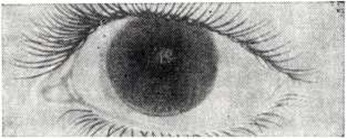

На ЭКГ выявляется диффузное поражение миокарда. Поражение органа зрения наблюдается у всех больных и является наиболее ранним и типичным симптомом заболевания.

У большинства больных развивается помутнение роговицы, которое возникает в глубоких слоях, а затем диффузно захватывает всю роговицу (рисунок 2). В отдельных случаях помутнение роговицы может быть выявлено с рождения. Нередко наблюдаются мегалокорнеа, врождённая глаукома, застойные явления и атрофия дисков зрительного нерва, пигментная дистрофия сетчатки.

Рис. 2. | ||